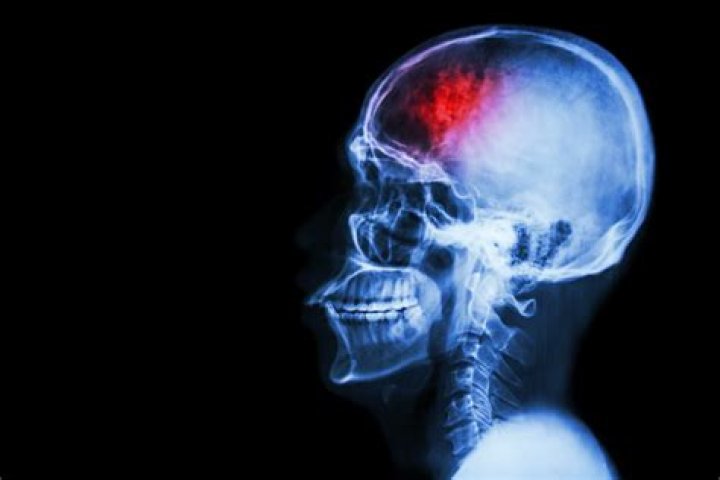

The OP has also attached an X-ray of the patient's skull, showing a long nail stuck inside the person's head. In the caption, the Reddit user provided some context to the story by writing the following: "So I work in an ER and a patient was working with a nail gun, heard it misfire, didn't notice anything, and came in hours later with a headache and bloody nose. Needless to say we were all surprised. It shot perfectly in his nostril and nestled into his brain."

Lateral skull X-ray from the side

Stock image: An image showing a lateral skull X-ray. A Reddit post has gone viral after a man had accidently shot a nail in his brain through his nostril. Stock image: An image showing a lateral skull X-ray. A Reddit post has gone viral after a man had accidently shot a nail in his brain through his nostril. Getty Images/stockdevil